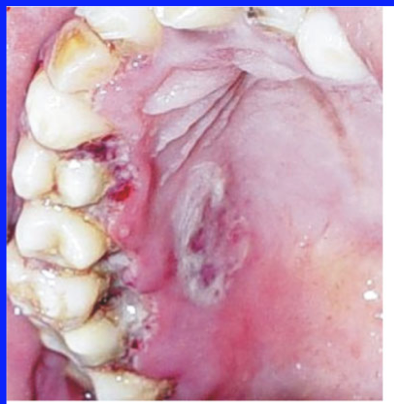

acute ulcerative gingivitis